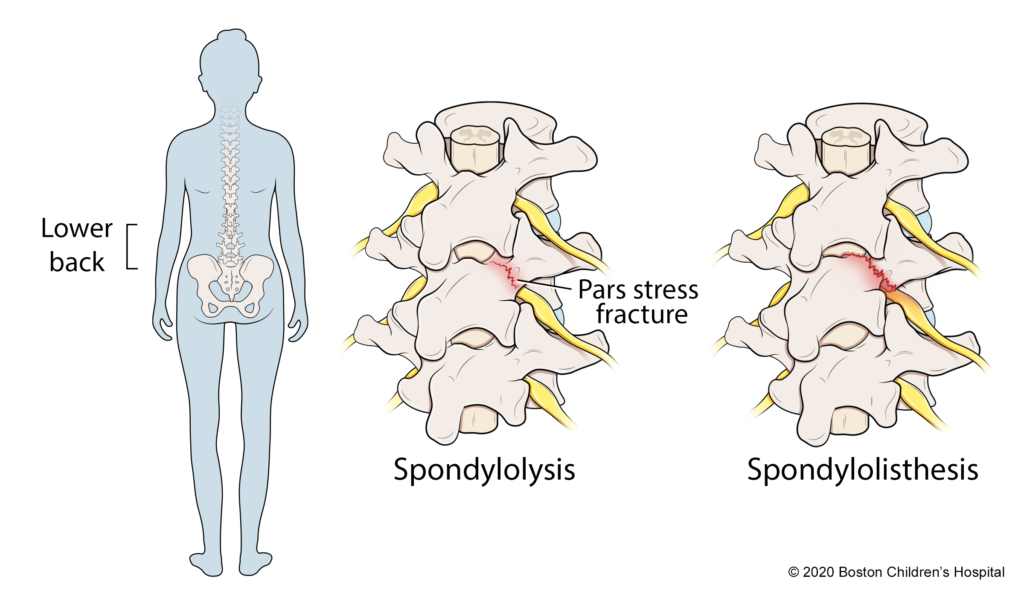

Spondylolysis :

Spondylolysis is a stress fracture or defect in the pars interarticularis – a thin part of the vertebra. Common in athletes or those with repetitive spine stress, it can lead to instability and, if it progresses, spondylolisthesis (vertebra slipping).

– Spondylolysis: Stress fracture in the vertebra.